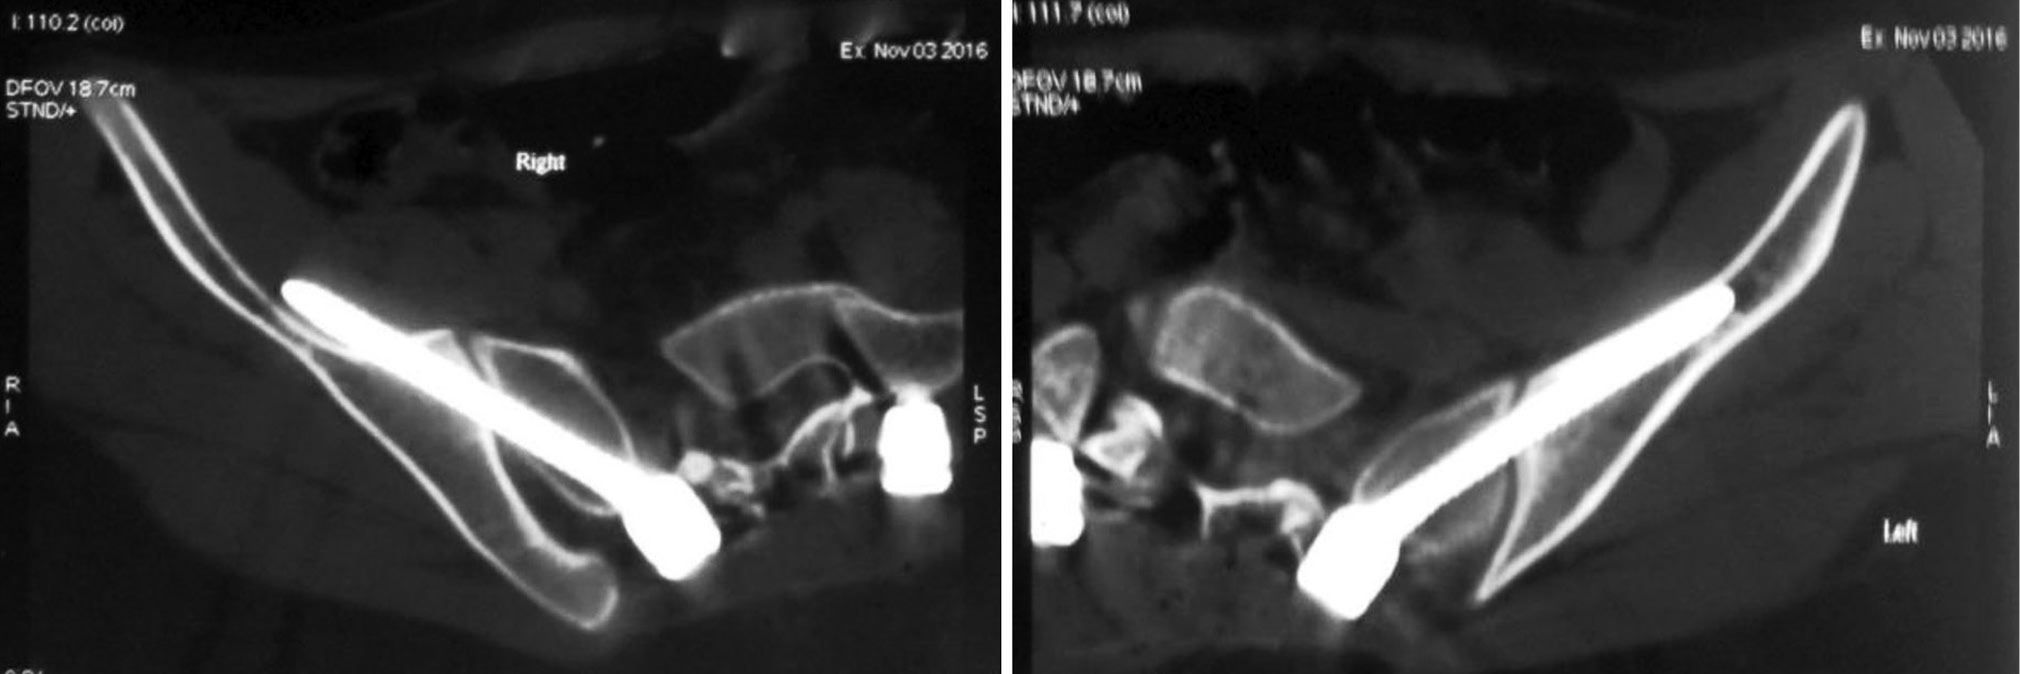

Жалоб и других клинических проявлений со стороны подвздошно-крестцовых сочленений не наблюдалось ни в одном случае. Отсутствие осложнений, потребовавших повторного оперативного лечения или повлиявших на результат лечения, и стабильная фиксация в отдаленном периоде наблюдения отмечена в 52 случаях (78,7 %). В 6 случаях по данным послеоперационной компьютерной томографии (КТ) выявлена мальпозиция винтов с перфорированием наружной кортикальной стенки подвздошной кости в 4 случаях, и в 2 случаях — винт выходил через медиальную кортикальную часть подвздошной кости (рис. 3). Во всех случаях за пределы костной ткани выходила дистальная часть винта, не превышающая одну треть от общей длины винта. В 2 случаях из вышеуказанных мальпозиций у пациентов с крайне тяжелым нейрогенным сколиозом на фоне ДЦП установка винтов была связана с техническими сложностями, в связи с гиперлордозом, сопровождающимся антеверсией таза на фоне двухсторонних разгибательных контрактур бедер. Контрольное КТ-исследование выявило у обоих пациентов выход винтов за наружные кортикальные пластины подвздошных костей. Клинически при этом никаких негативных проявлений не отмечено, реопераций не потребовалось.

Рис. 3. Односторонняя мальпозиция винта в подвздошной кости по данным компьютерной томогрфии с пенетрацией внутренней стенки, не повлиявшая на клинический результат операции и не потребовавшая повторной операции

Fig. 3. Unilateral malposition of the screw in the ilium according to CT with penetration of the inner wall, which did not affect the clinical outcome of the operation and did not require reoperation

Наибольшее число осложнений — перелом стержня металлоконструкции на уровне L5-S1 (15,2 %) (рис. 4), перелом винтов в подвздошных костях (5 %) и нестабильность фиксации с резорбцией костной ткани вокруг винтов в позвонке S1 и в подвздошных костях (3 %).

Рис. 4. Пациентка 55 лет. Идиопатический сколиоз: а — удовлетворительное положение винтов в подвздошных костях по данным компьютерной томографии с незначительной односторонней пенетрацией наружной стенки; b — перелом стержней металлоконструкции на уровне L5-S1 через год после операции, что потребовало повторного оперативного вмешательства

Fig. 4. Patient 55 years old, idiopathic scoliosis: a — satisfactory position of screws in the ilium according to CT with insignificant unilateral penetration of the outer wall; b — fracture of the metal rods at the L5-S1 level one year after the operation, which required repeated surgery